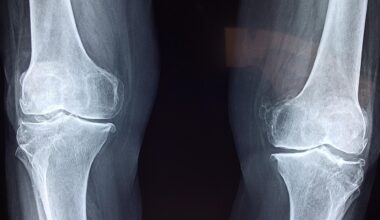

Maintaining optimal joint health is crucial for overall well-being and mobility as we age. Joints serve as the connection points between bones, enabling movement and providing stability to the skeletal structure. Over time, joints can undergo wear and tear due to factors such as aging, physical activity levels, and injury. These factors may lead to conditions like arthritis, causing pain and limiting mobility. Emphasizing functional training alongside a balanced diet rich in nutrients can significantly support joint health. Nutrients such as omega-3 fatty acids, glucosamine, and chondroitin are essential for maintaining cartilage health and reducing inflammation. Furthermore, staying active through low-impact activities like swimming or cycling can be beneficial, helping to maintain flexibility while minimizing stress on the joints. Engaging in targeted exercises enhances muscle strength, which in turn supports the joints and reduces the risk of injury. Many people overlook the importance of joint health until an issue arises; however, implementing preventative measures through functional training and healthy living can contribute greatly to long-term mobility and quality of life. Taking these steps early on is beneficial for longevity and physical capabilities.